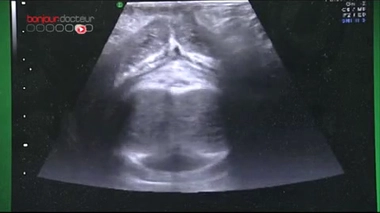

Echographie du point G